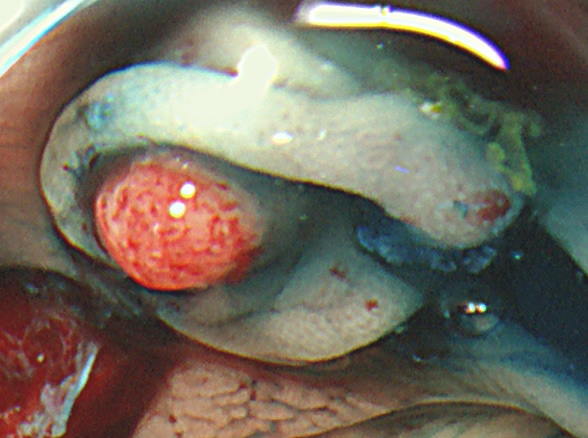

実際の写真です。

「生切り」なので、当然、内視鏡中(切除時)は出血します(患者さんが不安になります)。しかし、出血は数分で止まり、晩期出血は、まずありません。

取り残しを防ぐために、周囲に十分な余裕を持って大きく切除する必要があります(「ジャスト・サイズ」の傷では境界線上に腫瘍細胞が残ります)。そのために独特の「コツ」が必要で従来の方法よりも技術的に難しく時間がかかります。

コールド法で切除された検体は「目玉焼き」のようになります。「黄身」が病変で、「白み」が周囲の正常組織(余白、マージン)です。

腫瘍の取り残しを防ぐために「白み(余白)の大きな目玉焼き」にすることが、コールド法の最大のポイントであり、技術的に最も難しい部分です。